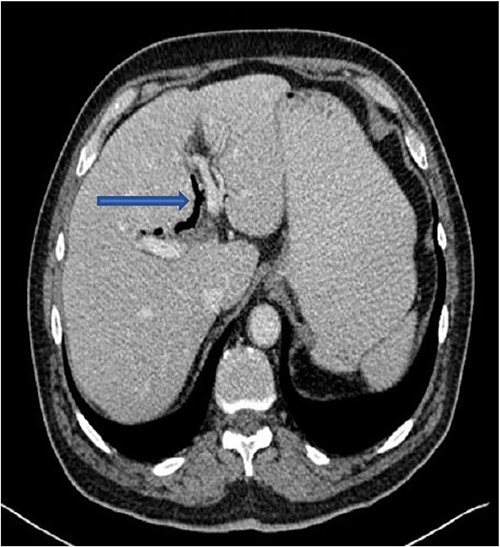

The plain film of the abdomen showed multiple air-fluid levels on the erect film (Fig. 1) and small bowel dilatation on the supine (Fig. 2). The CT showed multiple air pockets in the biliary tree, representing pneumobilia (Fig. 3). It also showed evidence of a circular radio-dense stone measuring 2 cm within the distal jejunum, leading to obstruction and dilatation of the proximal jejunum (Fig. 4).